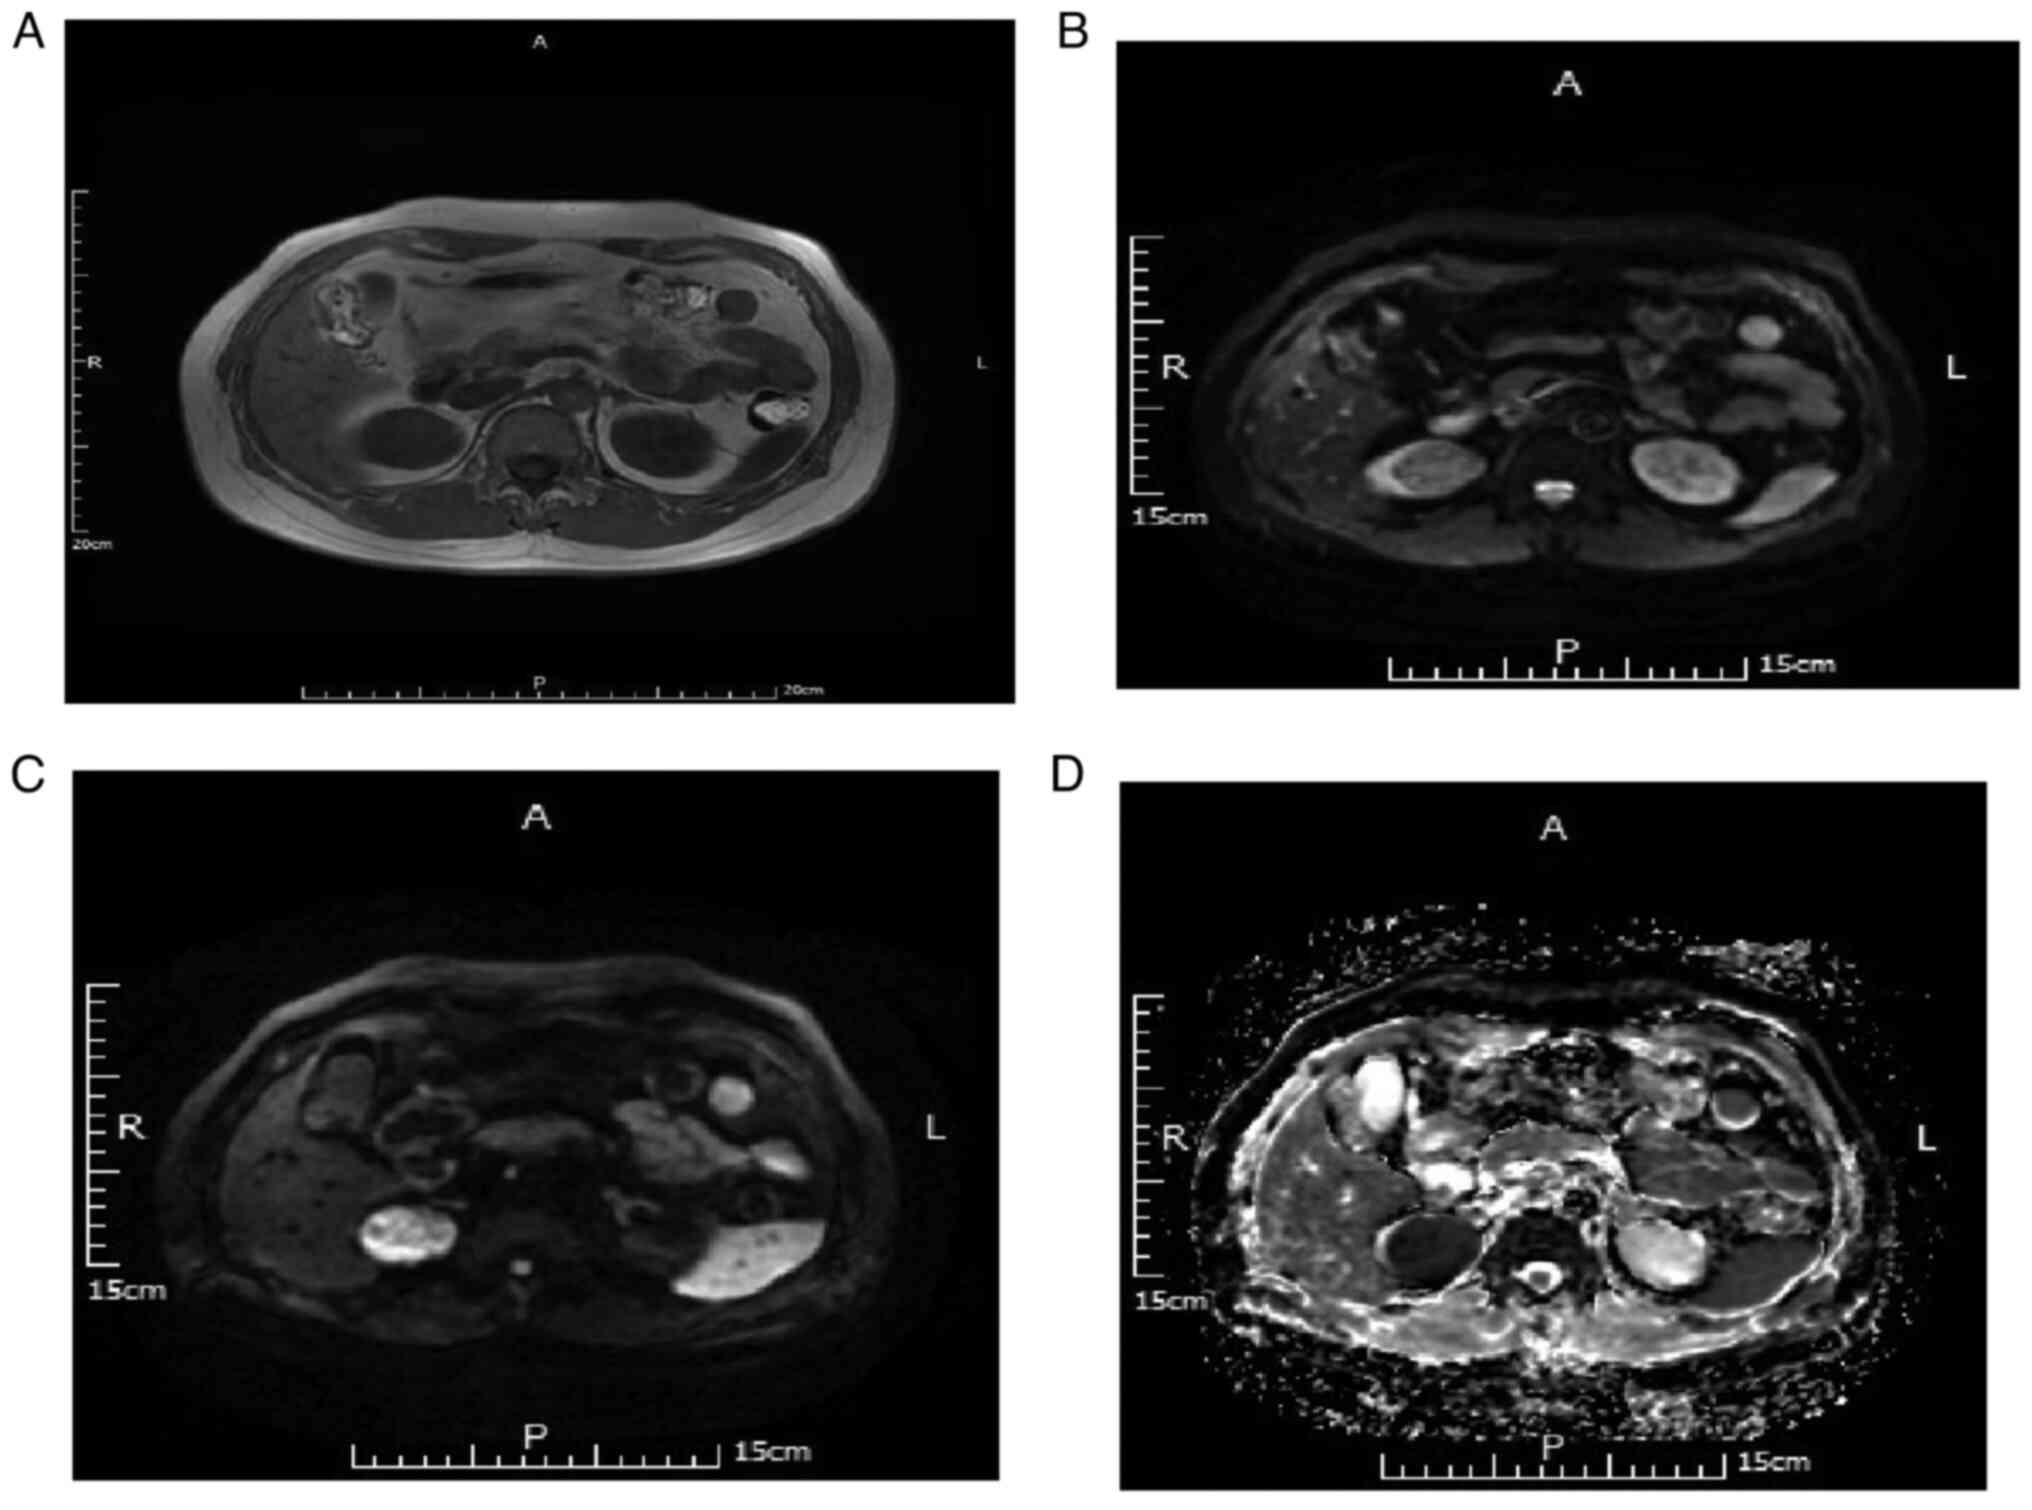

Imaging characteristics of DWI and ADC in the diagnosis of ccRCC

There were 68 cases of ccRCC. For DWI B-value=50 s/mm2, 52 of 68 cases (76.47%) were judged as slightly high and 16 cases (23.53%) as high signal. For DWI B-value=800 s/mm2, 19 cases (27.94%) were judged as slightly high, 16 cases (23.53%) as equal and 33 cases (48.53%) as low signal. Meanwhile, for ADC, 14 cases were judged as low signal (20.59%), 23 (33.82%) as equisignal and 31 cases (45.59%) as slightly high signal. Representative MRI scans are depicted in Fig. 4.

Figure 4.

MRI scans of a 62-year-old male with pathologically confirmed renal clear cell carcinoma of the left kidney. (A) T1WI, left renal tumor with low signal. (B) DWI B=50, left renal tumor with high and low confounding signal. (C) DWI B=800, left renal tumor with low confounding signal. (D) Apparent diffusion coefficient with slightly high signal. DWI, diffusion-weighted imaging.